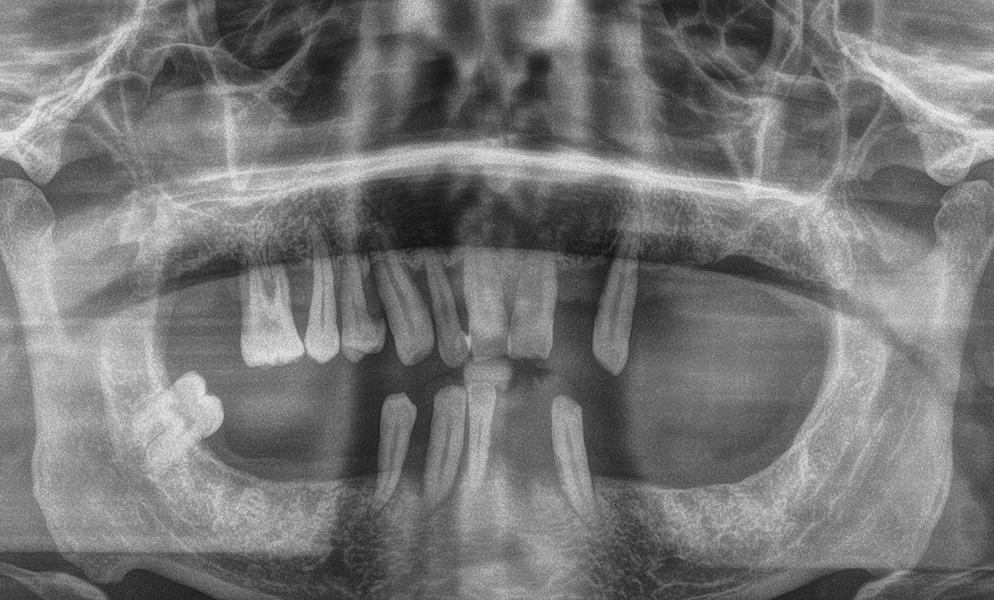

| Before | After |

![]() |

| Lower teeth extraction and immediate short dental implant (Bicon, USA)- placement | |